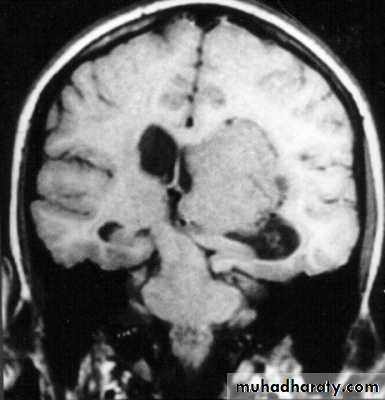

Investigations of Intracranial Hypertension

A. Skull X- RayB. Computed Tomography (CT Scan) of Brain.

C. Magnetic Resonance Imaging (MRI) of Brain